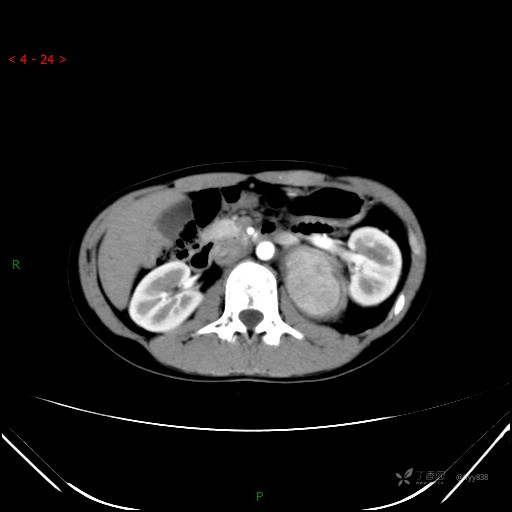

增强静脉期